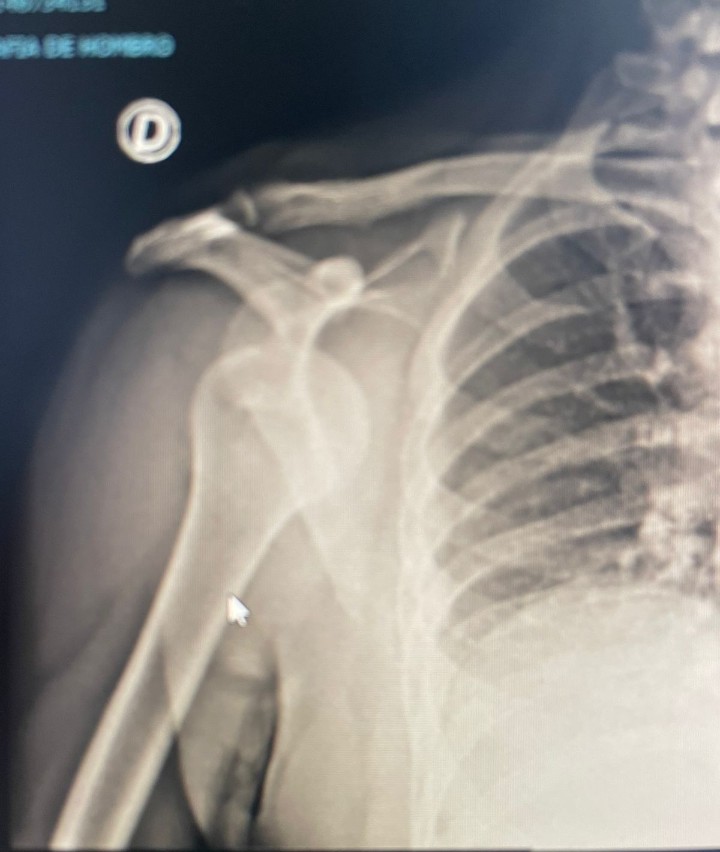

Son has dislocated his shoulder on a business trip abroad. He says he was playing padel .. ![]()